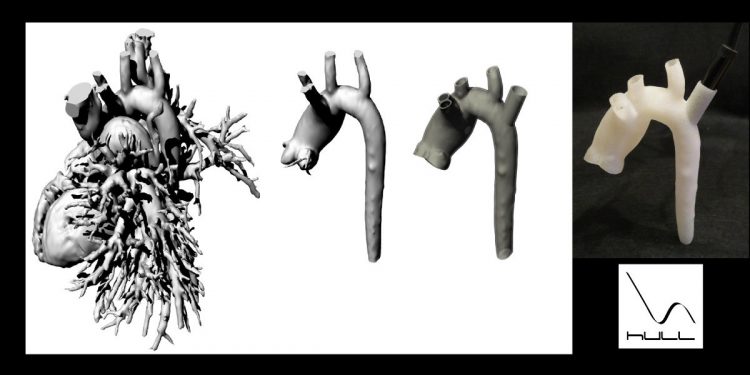

Este es el proceso que HullProject sigue para crear un biomodelo de la aorta a la que hemos añadido un […]

Descubre en este video cómo la fabricación de un biomodelo de aorta permite evaluar la colocación de un stent en […]